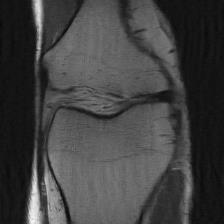

Recently, deep neural networks have greatly advanced undersampled Magnetic Resonance Image (MRI) reconstruction, wherein most studies follow the one-anatomy-one-network fashion, i.e., each expert network is trained and evaluated for a specific anatomy. Apart from inefficiency in training multiple independent models, such convention ignores the shared de-aliasing knowledge across various anatomies which can benefit each other. To explore the shared knowledge, one naive way is to combine all the data from various anatomies to train an all-round network. Unfortunately, despite the existence of the shared de-aliasing knowledge, we reveal that the exclusive knowledge across different anatomies can deteriorate specific reconstruction targets, yielding overall performance degradation. Observing this, in this study, we present a novel deep MRI reconstruction framework with both anatomy-shared and anatomy-specific parameterized learners, aiming to "seek common ground while reserving differences" across different anatomies.Particularly, the primary anatomy-shared learners are exposed to different anatomies to model flourishing shared knowledge, while the efficient anatomy-specific learners are trained with their target anatomy for exclusive knowledge. Four different implementations of anatomy-specific learners are presented and explored on the top of our framework in two MRI reconstruction networks. Comprehensive experiments on brain, knee and cardiac MRI datasets demonstrate that three of these learners are able to enhance reconstruction performance via multiple anatomy collaborative learning.